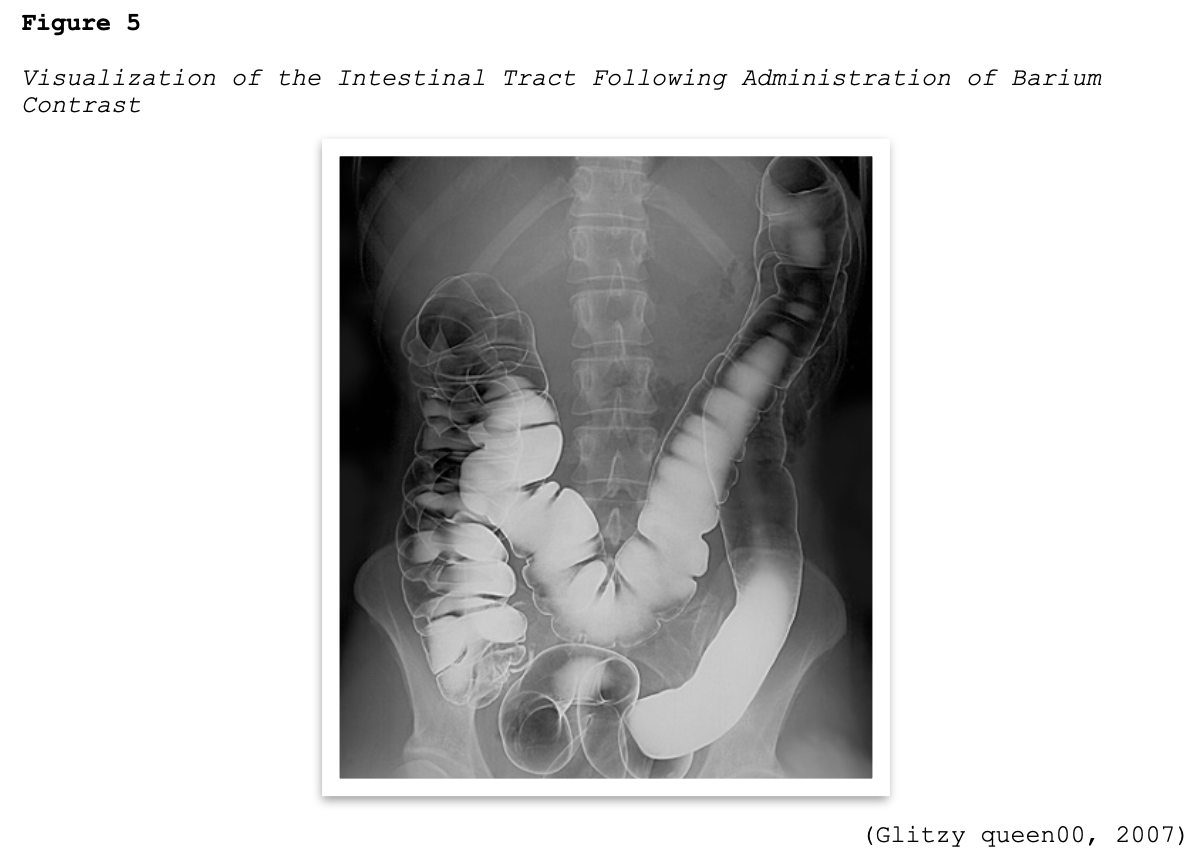

Barium sulfate contrast agents (BSCAs) are the preferred agents for evaluating and visualizing the GI tract and can only be administered through the GI tract, which includes the oral and rectal routes (ACR, 2020). They are comprised of a suspension of insoluble barium sulfate particles that are not absorbed by the gut and are ideal for illuminating the GI tract since they have excellent coating properties of the GI mucosa, as demonstrated in Figure 5. They are the most common type of orally administered contrast material and enhance the visualization of the GI tract in CT scans of the abdomen and pelvis and specific types of MRI scans. They are also commonly used for fluoroscopic studies, such as an upper gastrointestinal (UGI) series or a small bowel follow-through (SBFT) examination. BSCAs are also used in patients undergoing GI studies that can be performed via nasogastric tubes, as well as via the rectal route during fluoroscopic studies evaluating the colon (RadiologyInfo.org, 2018).